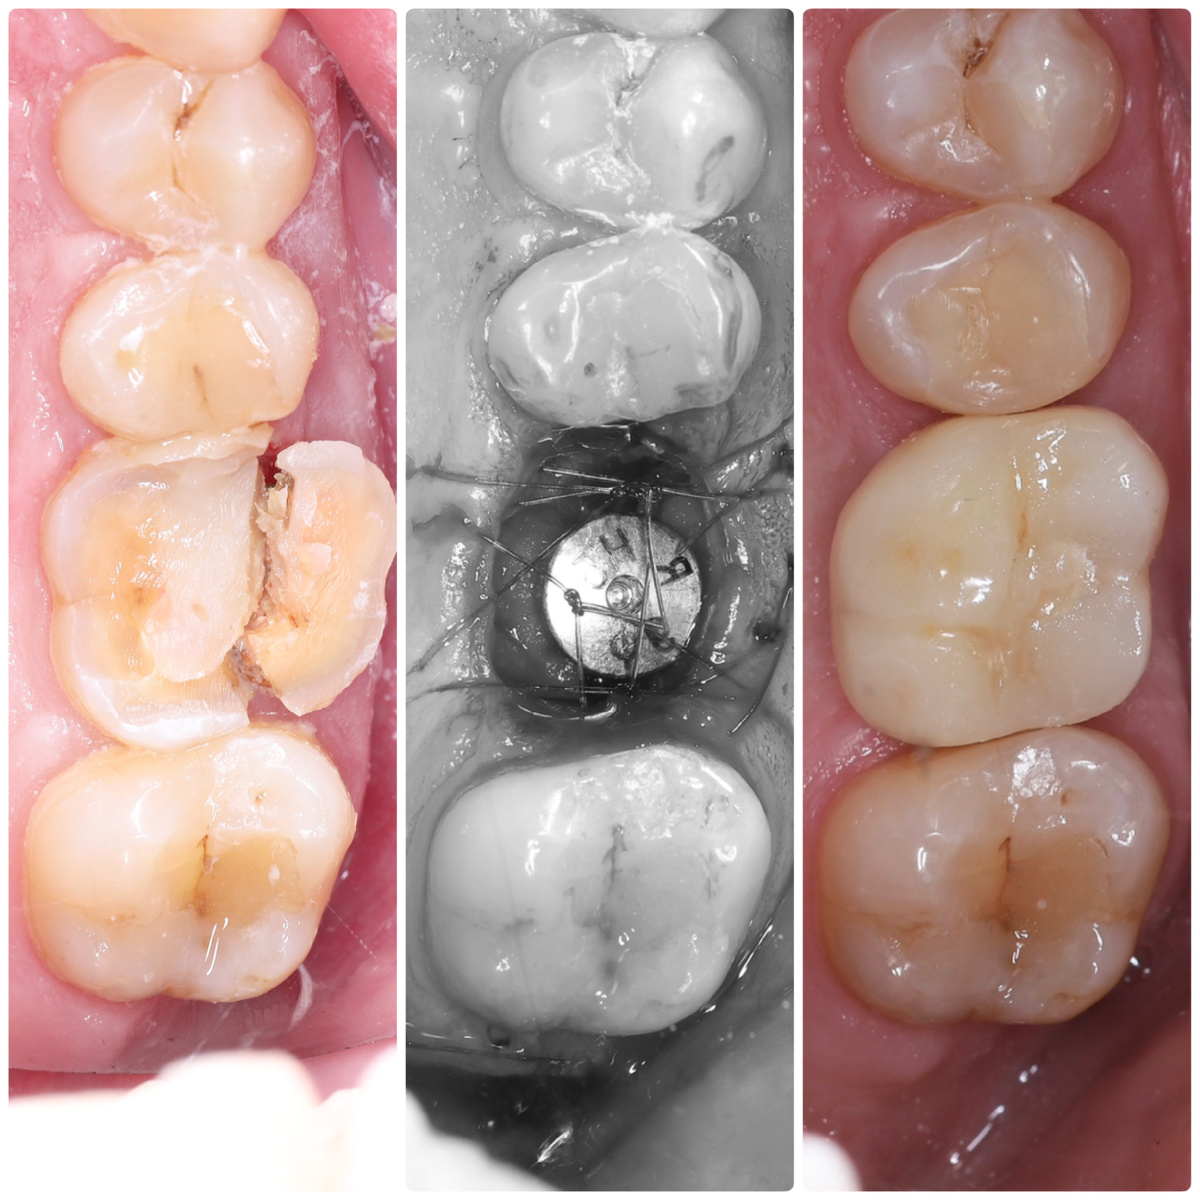

Одномоментная имплантация в области 1.6 зуба. До / после операции / после фиксации постоянной коронки (через 3 месяца)